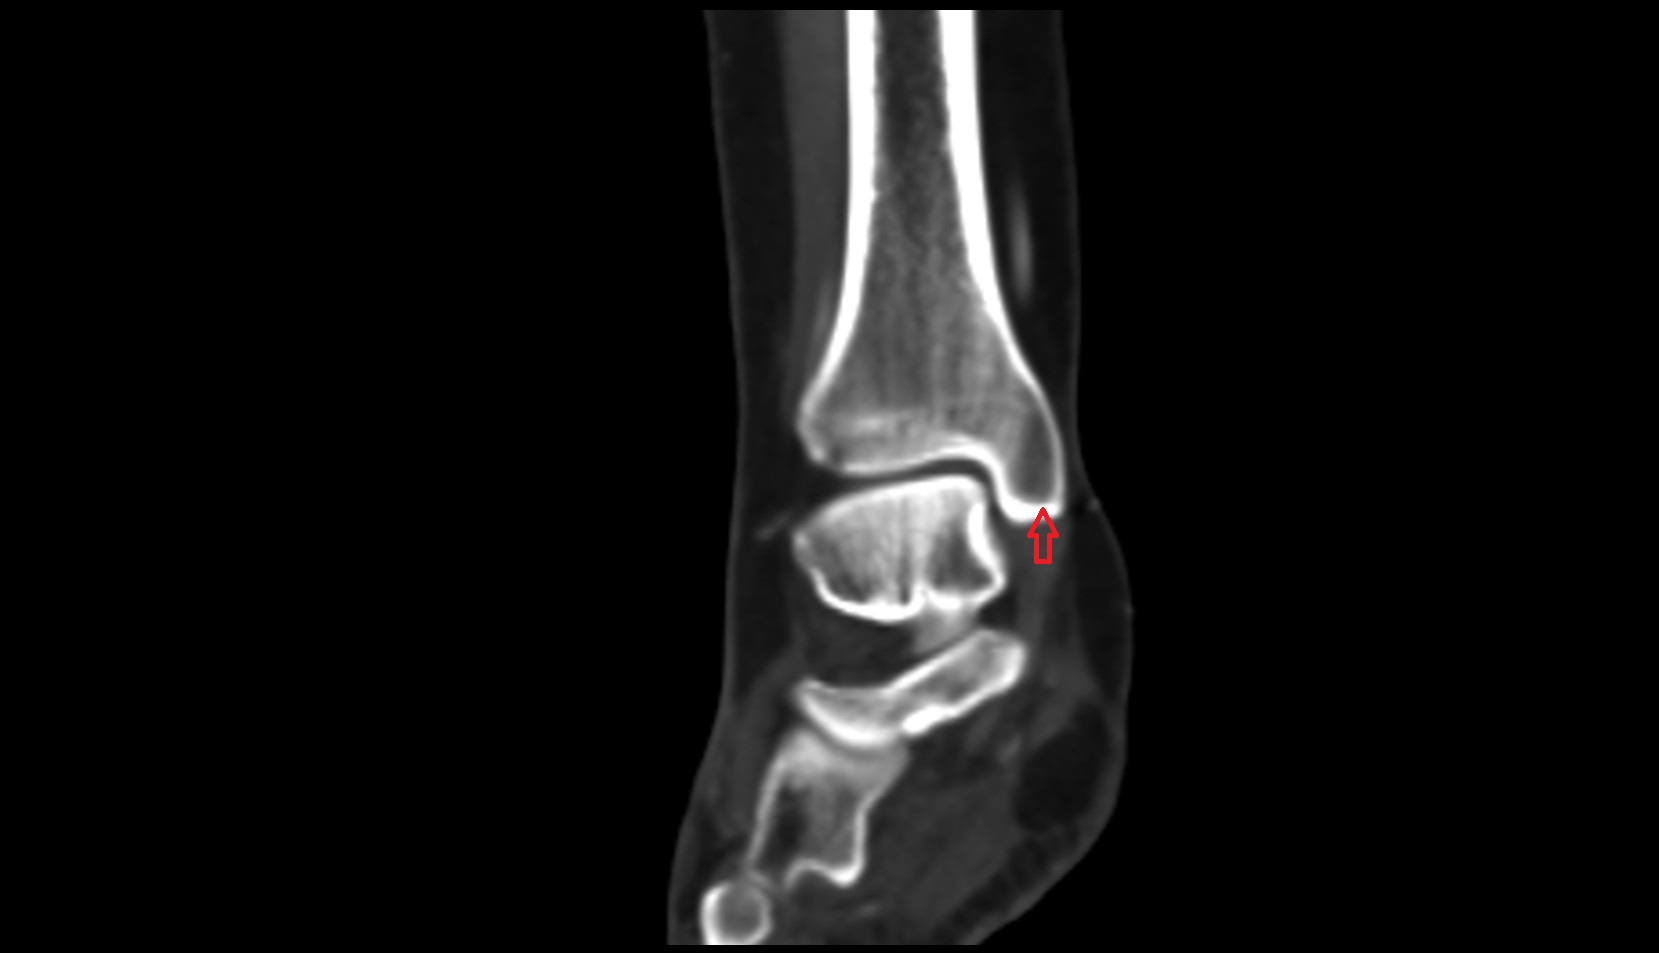

- Ankle joint

- Talus

- Body of talus

- Neck of talus

- Medial malleolus

- Lateral malleolus

- Anterior talofibular ligament

- Posterior talofibular ligament